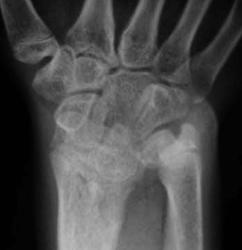

Девочка 14 лет. Ранее за помощью не обращались. Только в этом возрасте родителей и саму пациентку начала беспокоить деформация предплечий.

Рентгенологическая классика для болезни Маделунга:

1. Укорочение лучевой кости.

2. «Скошенность» суставной поверхности дистального эпифиза лучевой кости в ладонную и локтевую сторону, что «симулирует» визуально подвывих костей запястья.

3. «Нависание» полулунной кости над ладонным краем дистального эпифиза лучевой кости.

4. Высота дистального эпифиза по лучевой стороне превосходит его высоту по локтевой стороне.

5. В результате раннего закрытия ростковой зоны по локтевой и ладонной стороне, формируется ладонный и локтевой наклон суставной поверхности.

6. Деформация и изменение расположения проксимального ряда костей запястья, по форме, напоминающей «клин», вершиной которого является полулунная кость.

7. Головка локтевой кости находится в положении «вывиха» и смещена в «тыльном» направлении, по отношению к лучезапястному суставу.